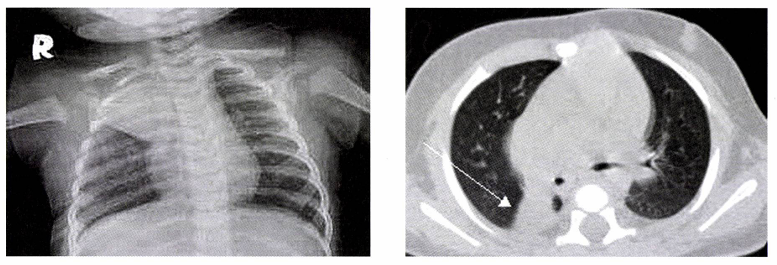

• 영상 검사

• 흉부 X선: 폐 용적 감소, 폐엽간열(lung fissure)의 위치 변동 관찰

• 흉부 CT (특히 HRCT): 폐쇄 원인 감별 및 무기폐의 정확한 범위 평가에 유용함.